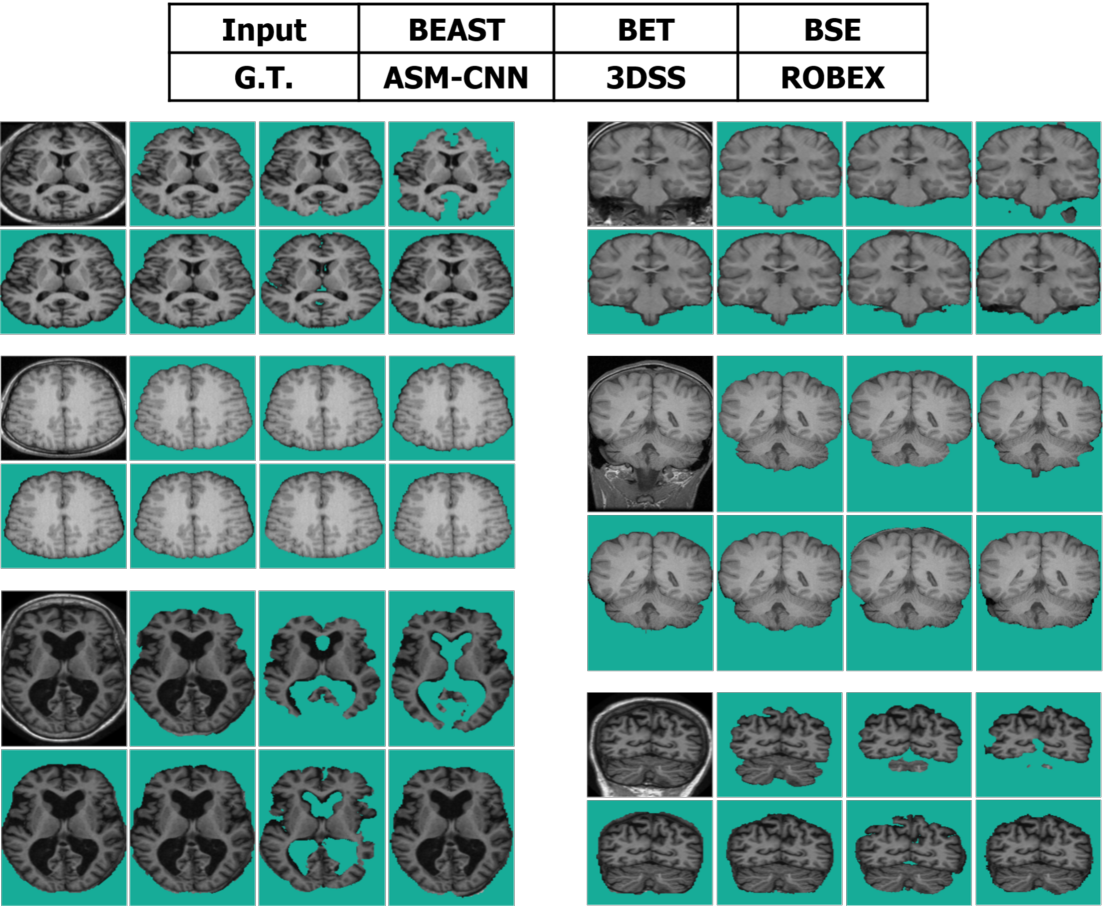

Refer to caption

Figure 11: The comparison between ASMCNN with other methods on IBSR dataset.

Segmentation results of ASMCNN and seven other methods in the sagittal plane for the three datasets are illustrated in Figures 11, 12 and 13 respectively. Each figure includes six typical testing scans from all three groups (two scans for each group). Although ASMCNN works with the sagittal plane, it also produces correct segmentation in two other planes. Figure 14 shows the comparison between our approach and other methods on each dataset for these two planes.

ASMCNN can provide extremely accurate segmentation in these three datasets. We achieve the same results as ROBEX with smooth boundaries and keep both gray and dura matter inside extracted brains for most cases, which are usually left out by ROBEX. Although there are minor leakages into the skull by ASMCNN, its occurrence is less than both ROBEX and BEAST, as it only generates a smaller number of over-segmentation results. The critical impact of the method is that it can precisely work for small-size brains in Group I as well, meanwhile other techniques usually fail. As shown in Figures 11 - 13, our results are mostly similar to the ground-truth images especially for tiny-size brains (Figure 11). The method does not avoid a few false negatives and false positives in this group on account of the complexity of the brain structure. Nevertheless, ASMCNN can mostly obtain a better performance than others with higher accuracy.